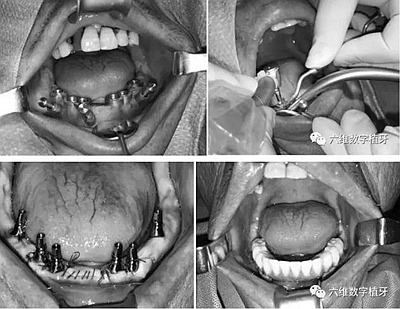

導(dǎo)航手術(shù)過程照片

通過術(shù)前精確的設(shè)計(jì),避開了患者骨壁較薄需要做骨劈開的區(qū)域,避免了大翻瓣造成較大創(chuàng)傷,大大提高了患者的舒適度。

全程手術(shù)采用小翻瓣微創(chuàng)種植,選擇初期穩(wěn)定性較好的植體進(jìn)行即刻負(fù)重。整個(gè)手術(shù)從開始到最終戴上臨時(shí)牙,只花費(fèi)2個(gè)小時(shí)的時(shí)間,就讓患者恢復(fù)了完美笑容。數(shù)字化種植為醫(yī)生和患者帶來不一樣的感受!